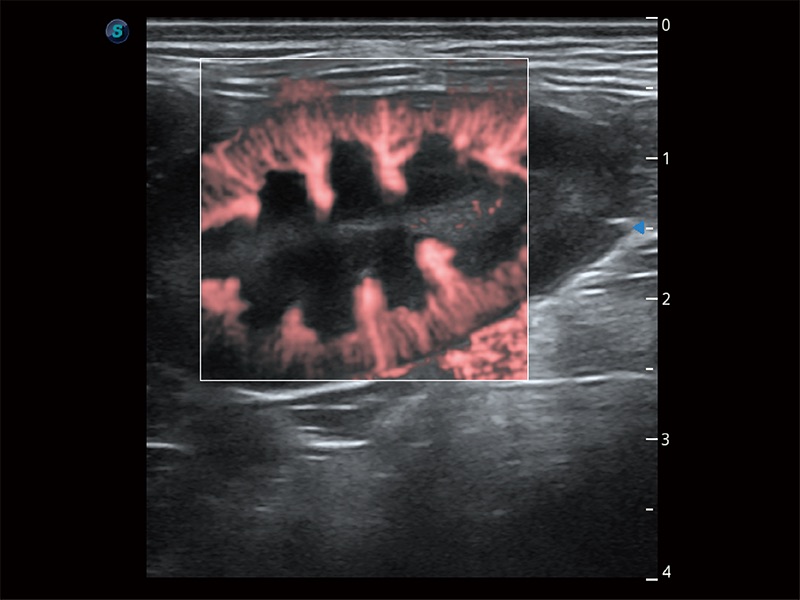

极大提升超低速微细血流的检出能力,同时更精准地滤除软组织和超声信号,为兽用医生提供以往无法通过常规血流获得的疾病诊断信息。

在传统二维血流成像的基础上,呈现血流的立体感,具有动感的生命力之美。即便是微小的血管也能轻松应对,提高了血流的视觉敏感性。

操作简便,无需高频度外力作用即可真实反映组织的形变,快速评估肿瘤良恶性。